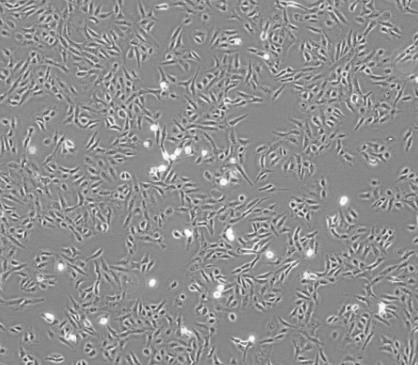

形态特征:HSC-4人口腔鳞癌细胞呈多角形或长条形,大小不一,有明显的核仁和胞质。

HSC-4人口腔鳞癌细胞系的形态为上皮细胞样,具有贴壁生长的特性。这些细胞可以用于研究口腔鳞状细胞癌的生物学特性、药物筛选和肿瘤治疗等方面的实验。通过观察细胞的生长、增殖和凋亡等生物学行为,可以深入了解口腔鳞状细胞癌的发生、发展和转移机制,为口腔鳞状细胞癌的诊断和治疗提供新的思路和方法。